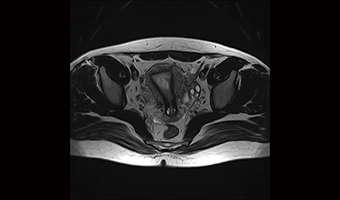

Application Images

Real 24/32 Channel System

By utilizing CSPI acceleration, it is possible to complete breath-hold abdominal high-speed high-resolution sequences.